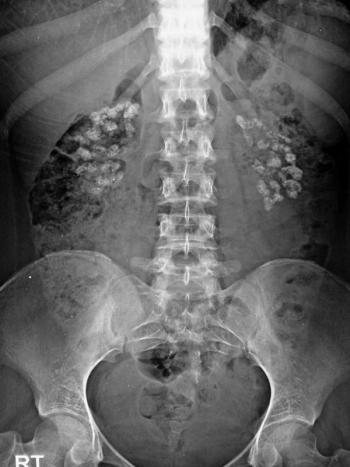

Image IQ Quiz: Patient Presents with Hyperparathyroidism

What's your diagnosis of this X-ray?